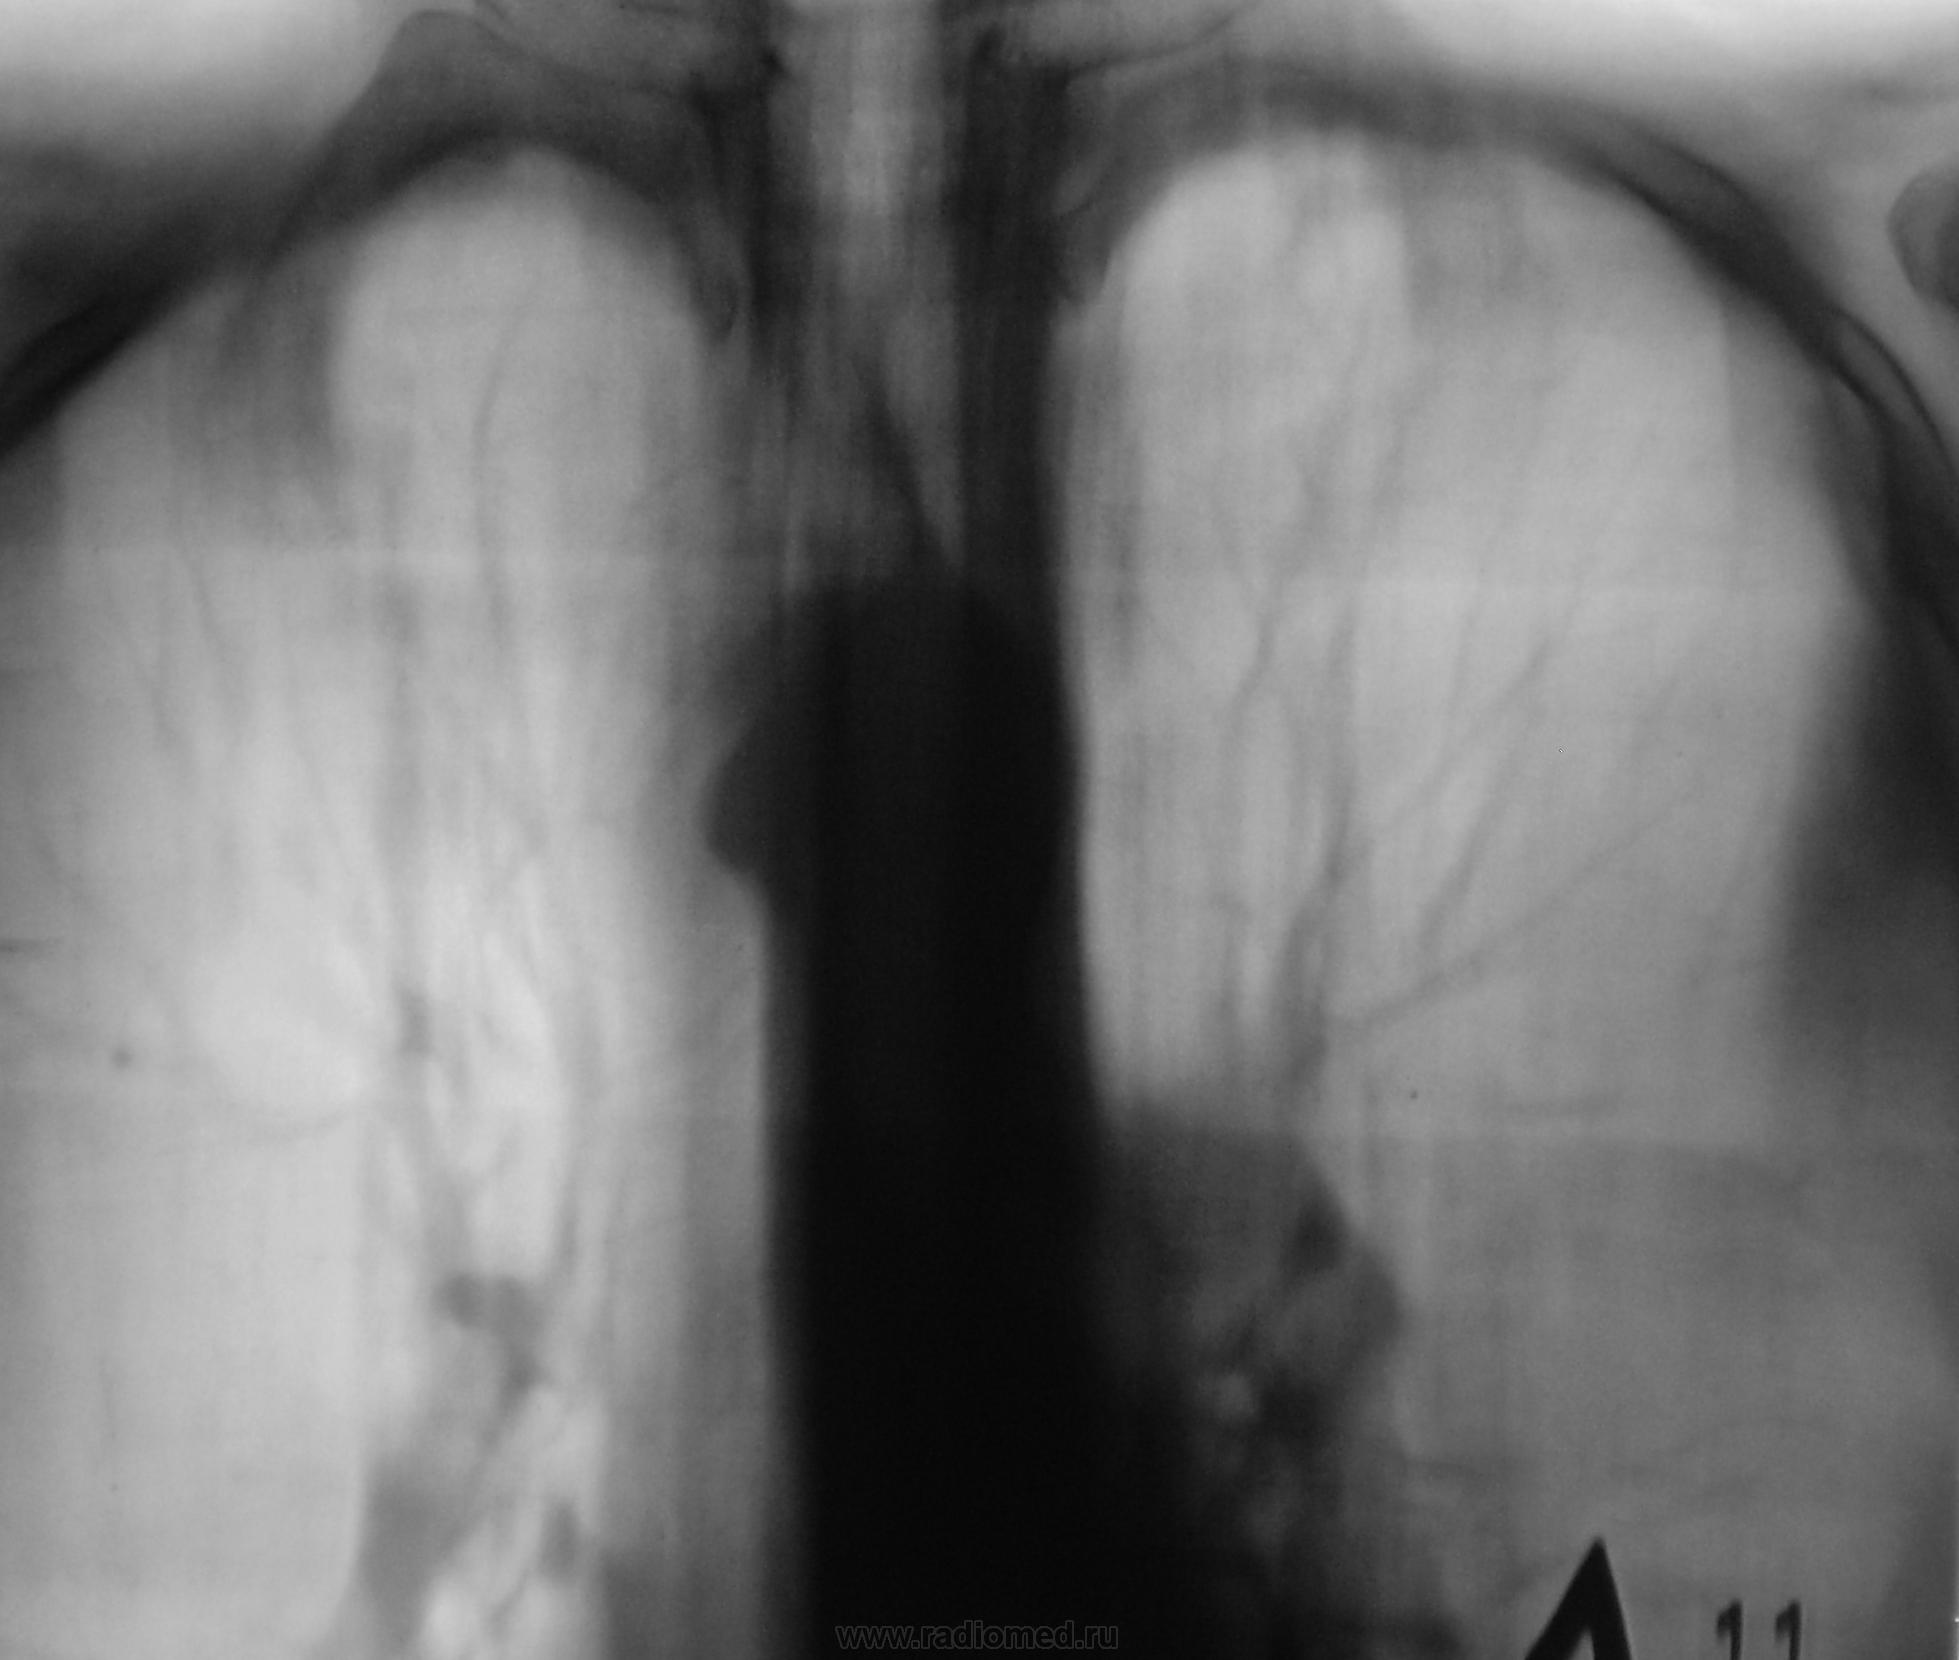

Мы, расценили ту «круглую тенюху» (тенюха ниже – 2 снимка), как туберкулому тоже настаивая на консультации фтизиатра.

Кстати, в тенюхе, тот «У» - образный «распад» (хотя, на мой взгляд, таким распад быть не может), которым интересовался коллега Nikolas, по поводу иллюстрации приведенной в монографическом источнике (иллюстрация ниже).

представленный Валентином Львовичем и дальнейшая  отрицательная динамика туберкулезного процесса, указывает нам на прогрессирование туберкулёмы. Вспышку туберкулёзного процесса подтверждает плевральный выпот слева. Следовательно, "Y- образный распад" в туберкулёме необходимо рассматривать как активный процесс. Необходимо накапливать материалы по этой теме. Благодарю В.Л. Катенёва за редкое, важное и поучительное для врачей различных специальностей клиническое наблюдение. С уважением Nikolas

Прошло 2 года с небольшим.